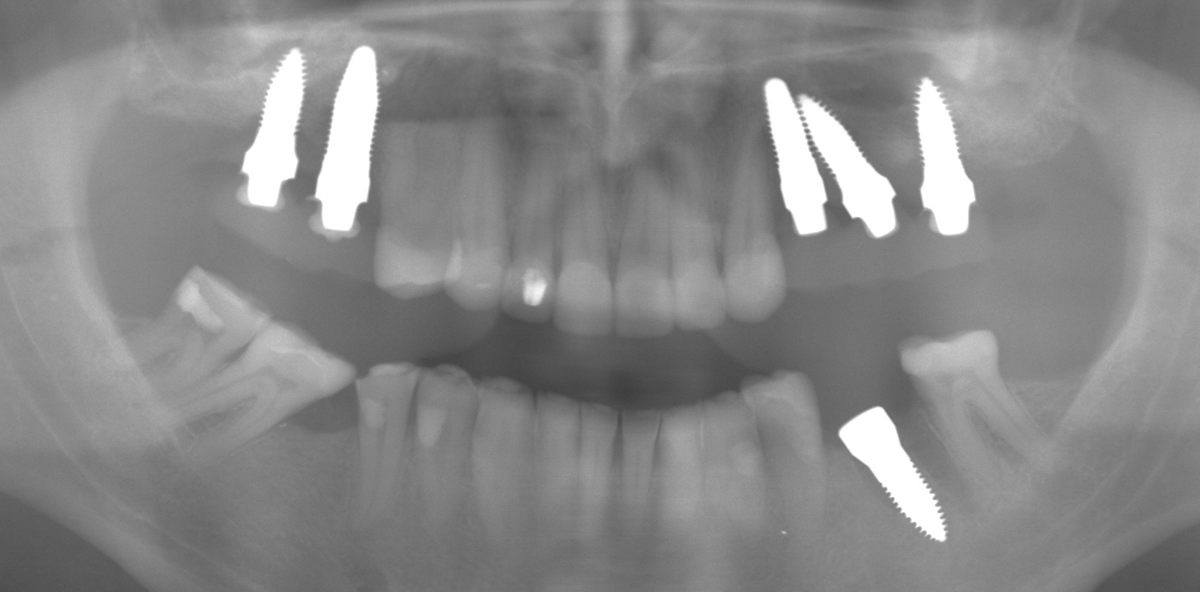

Im Vorfeld wurden operationsrelevante Daten abgeklärt, vor allem, um welches Implantatsystem es sich in seinem Fall handelte. In Regio 16, 25, 26 waren ANKYLOS® Implantate in situ, Regio 15 und 24 waren mit NobelActive™ Implantaten versorgt worden.

Die Explantation stellte sich als äußerst schwierig dar, da sich die beiden NobelActive™ Implantate weder mit dem Explantationstool der Firma BTI noch mit dem Fixture Remover Kit der Firma Neobiotech (Südkorea) entfernen ließen. Die übrigen drei ANKYLOS® Implantate wurden jeweils mit einem Drehmoment von ca. 250 Ncm entfernt. Die beiden NobelActive™ Implantate wurden in mühevoller Feinarbeit mit Extraktionsansätzen des Mectron PIEZOSURGERY® Gerätes unter maximaler Knochenschonung entfernt. Andernfalls wäre eine sofortige Implantation mit Keramikimplantaten nicht möglich gewesen.

Die Sofortimplantation erfolgte anschließend in die entstandenen Explantationsalveolen Regio 16, 15, 24, 26. Da das alte Implantat Regio 25 komplett außerhalb des Kieferkammes, prothetisch mangelhaft, inseriert worden war, musste eine neue Bohrung für das neue Implantat erfolgen. Da ein Sinuslift für die Sofortversorgung nicht infrage kam, wurde das Implantat 25 exzentrisch anguliert an der medialen Kieferhöhlenwand entlang inseriert. Eine Achsabweichung von bis zu 25 Grad ist mit den Implantaten der Firma SDS ohne Probleme durch direktes Beschleifen des Implantates möglich.

Zum Einsatz kamen die SDS-Implantate im Root Design (SDS RD ATZ), die auch bis zu einem Durchmesser von 5,4 mm verfügbar sind. Diese wurden alle mit demselben Drehmoment von ca. 35 Ncm primärstabil inseriert. Lediglich in den Bereichen 15 und 24 kam jeweils eine Haltnaht (PTFE) zum Einsatz. Die SDS-Zirkonimplantate wurden mit Rotringdiamanten präpariert und dabei in der Achsabweichung korrigiert. Mittels einer Tiefziehfolie (Formteil) wurden die Provisorien aus Protemp® 4 (3M ESPE) chairside gefertigt und mit Durelon® (Carboxylatzement der Firma 3M ESPE) eingesetzt. Die provisorische Versorgung war beidseitig außer Funktion eingeschliffen worden, um jegliche Überbelastung zu vermeiden. Der Patient wurde darauf hingewiesen, die Provisorien kaum zu belasten und nur weiche Kost zu sich zu nehmen. Trotz langer Operationsdauer hatte der Patient am Folgetag keine Schmerzen und auch keine Schwellungen.